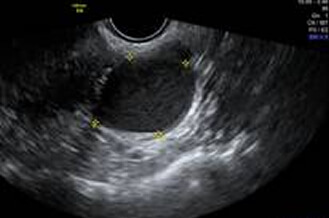

正常子宮